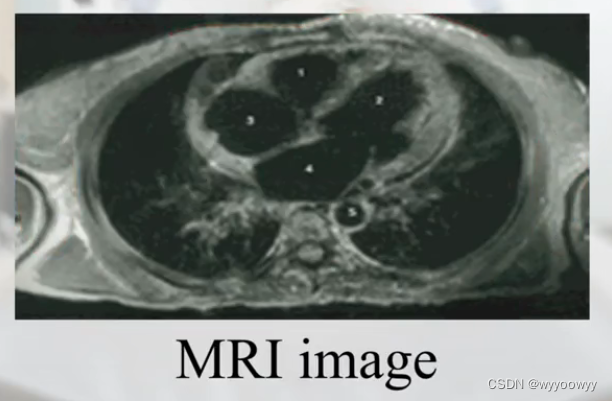

核磁共振图片